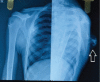

Case report: We have included five cases of osteochondromas occurring at rare locations with variable presentations and their management. We have included one case of metacarpal, one case of skull exostosis, two cases of scapula exostosis, and one case of fibula exostosis.